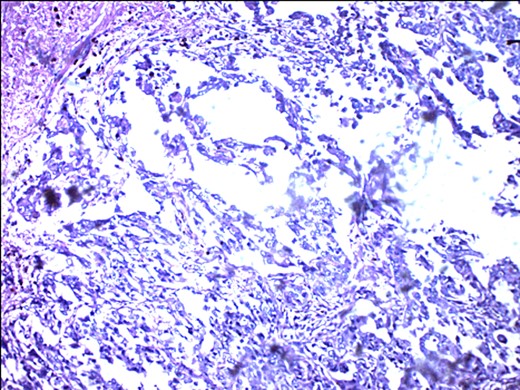

A 57-year-old woman presented with 5/12 history of left breast lump which gradually increase in size and became painful. Menarche was at 13 years without oral contraception. She had four confinements, the first being 20 years. Each child was breastfed for 8 months. No family history of breast cancer. Clinical examination showed breast asymmetry. Left breast was oedematous, shiny with extensive peau d'orange. Patient applied herbal preparations with multiple superficial skin excoriations. Outer quadrant breast mass was 8 cm, hard, with attachment to skin and underlying structures. No palpable axillary lymph node was felt and axillary ultrasonography, though desirable, was not done. Liver was not enlarged. Chest X-ray and abdominal ultrasound scan showed no involvement. Initial breast biopsy revealed an infiltrating atypical spindled tumour with hyperchromatic nuclei, which was both S100 and tyrosinase-positive. Tumour fungated with a darkly pigmented surface despite two cycles of neoadjuvant doxorubicin-based chemotherapy. Left simple mastectomy (Fig. 1) and axillary sampling (Fig. 2) of the sentinel and another slightly enlarged node were done, revealed a triple-negative invasive ductal carcinoma (Figs 3–6), with melanocytic differentiation (Figs 7 and 8), positivity for S-100 and patchy positivity for tyrosinase, an enzyme involved in melanin formation from dihydroxyl phenyl alanine. Only the sentinel node was involved, with the other showing reactive changes. Core biopsy of the tumour had ductal elements and was triple-negative.

ER negativity for rabbit monoclonal antibodies. Few stromal cells are positive black.